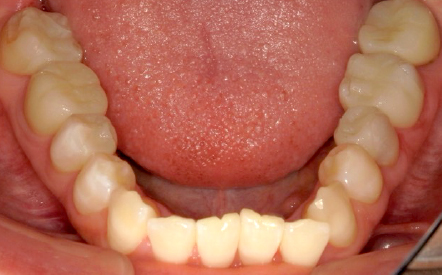

Before

After

30代女性 治療期間:2か月半 費用:168万円 (税込)

全顎的に不良補綴物を外し、カリエス(虫歯)を除去。中心位(顎関節による決定する顎位)にて咬合採得を行い、ジルコニアにて修復を行いました。現在、咬合、機能、審美、ともに全く問題なく経過しています。